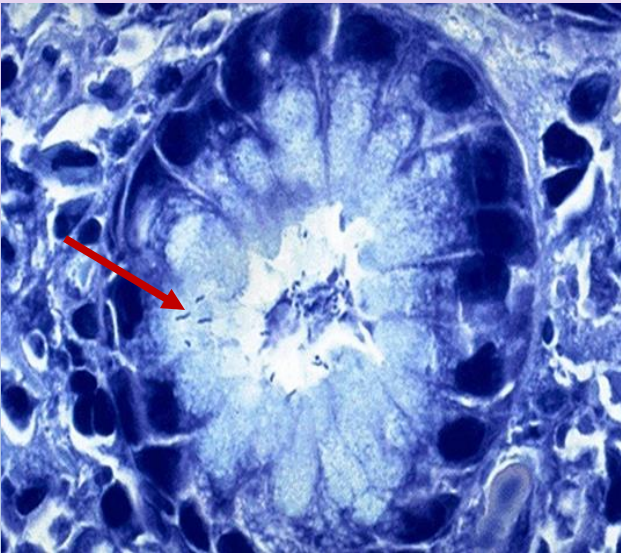

23

Q

Diagnose

Describe

Behavior

Arrow?

Reason cells look the way they do?

A

Stomach, Signet Ring Carcinoma

Invasion by MALIGNANT TUMOR composed of signet ring cells. These cells are poorly cohesive and have clear cytoplasm with dark eccentric nuclei

Malignant

Signet ring cells

Due to cytoplasmic mucin pushing nucleus to side